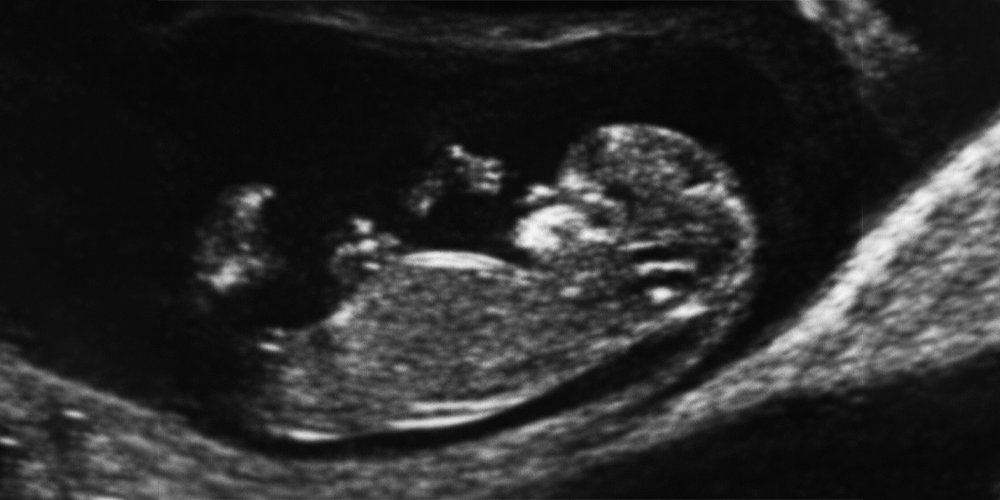

Bu haftaya kadar gelebilmiş olan gebeliklerde ilk anomali muayenesi yapılır. Bu büyüklükteki bir bebekte saptanabilecek ağır anomaliler mevcuttur. Örneğin beyin dokusunun hiç oluşmamaış olması, veya kafatası oluşmadığı için beyin dokusunun açıkta kalması gibi... Veya karın duvarının açık kalıp barsakların karın dışına taşması, bacakların gelişmeyip yapışık kalması gibi...

Neyse ki bu durumlar çok seyrektir. Yaptığımız muayenelerin hemen hemen tamamında (çok az istisna hariç) bir anomali görmeyiz.